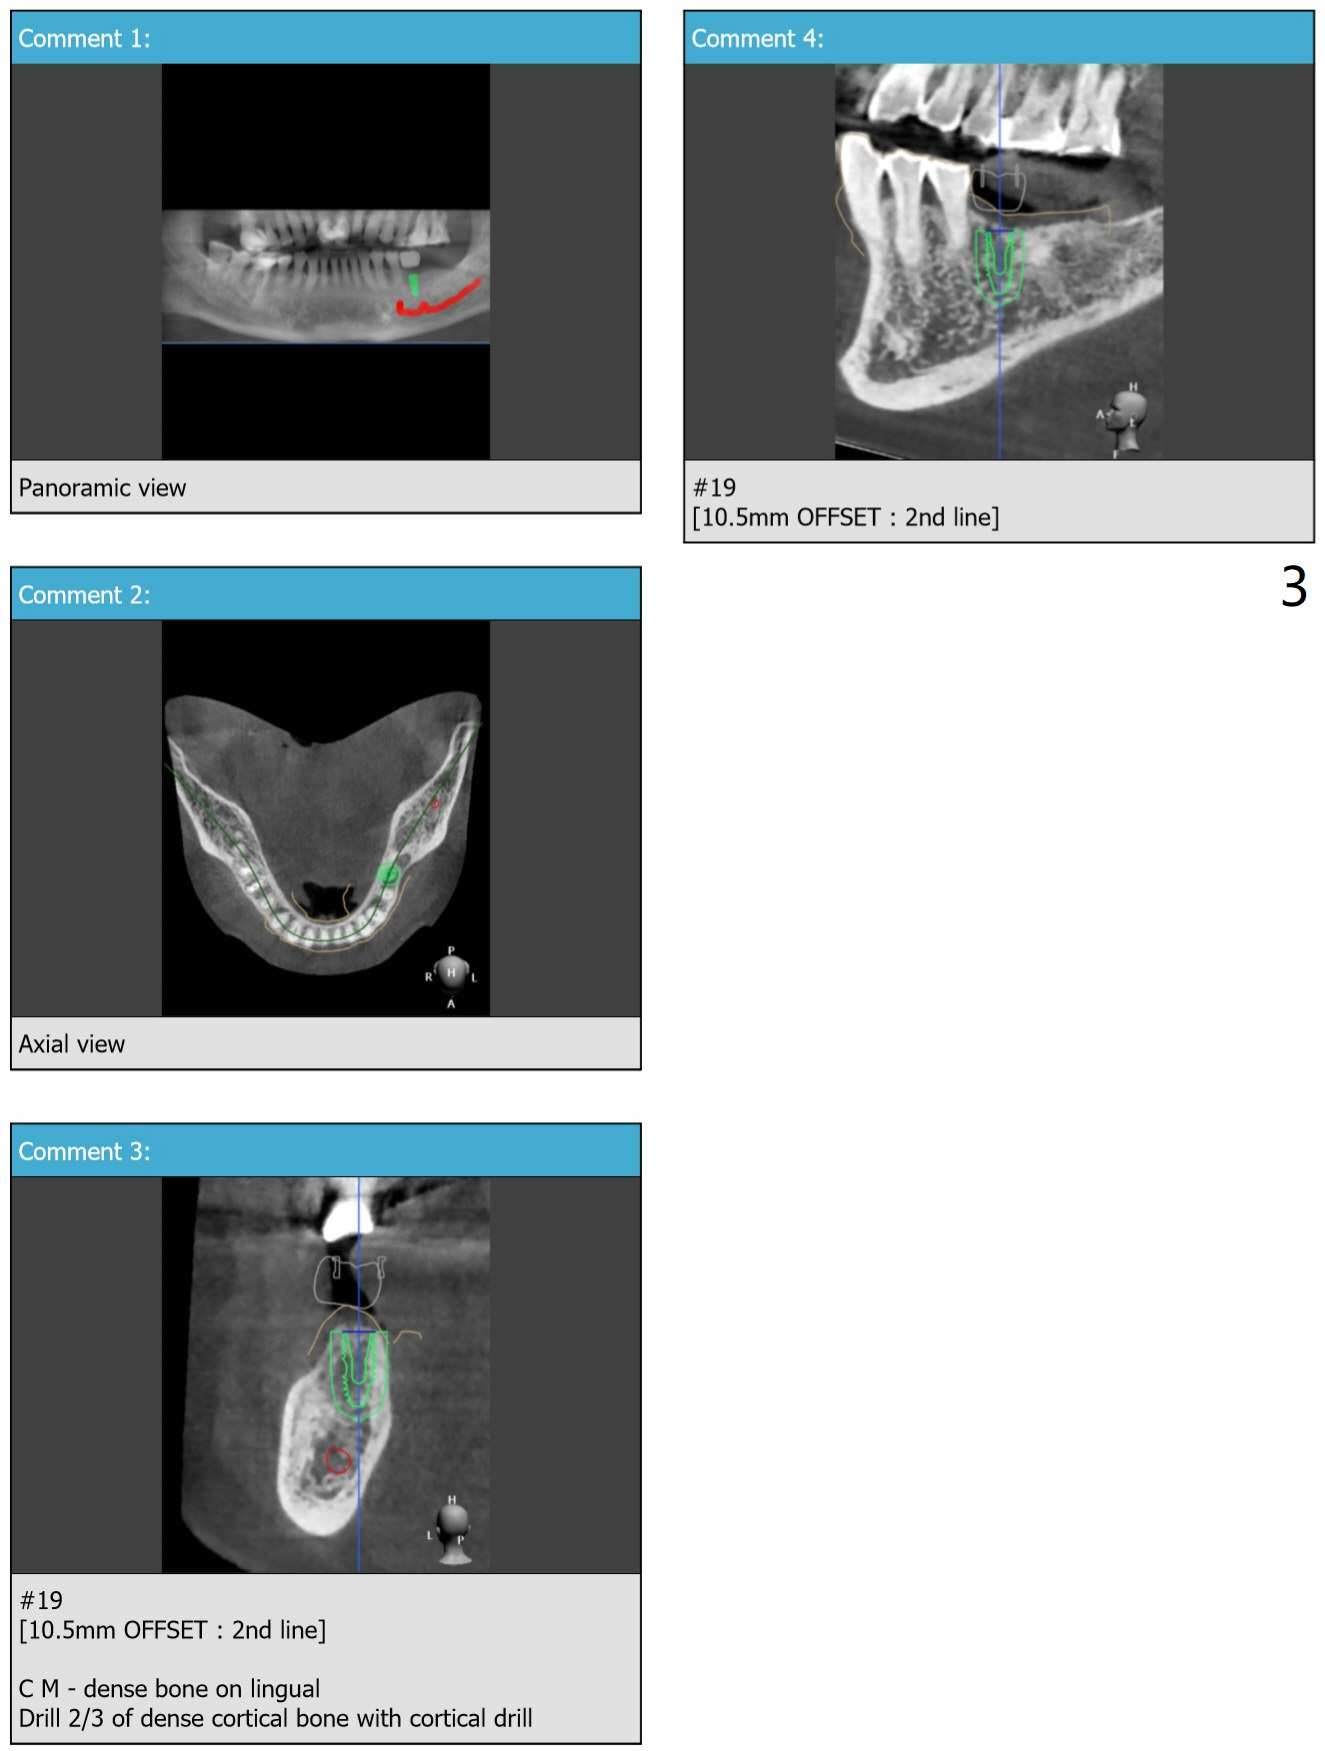

Lingual Placement  (M)

Return to Lower Molar Immediate Implant No Deviation